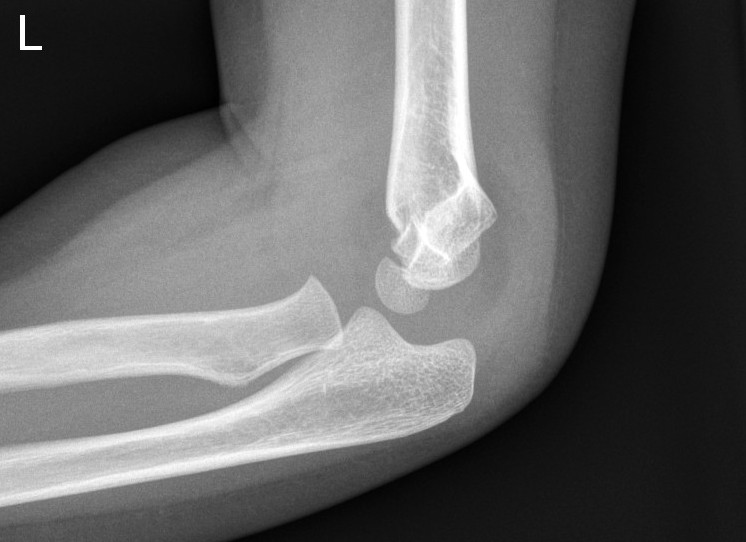

What Is A Fat Pad In The Elbow . Three paediatric orthopaedic trauma and elbow surgeons and two trained researchers (blinded to the respondents’ answers) independently. The posterior fat pad sign is the visualization of a lucent crescent of fat located in the olecranon fossa on a true lateral view of an elbow joint with the elbow flexed at a right angle indicating an. This could be due to swelling in that area of the elbow. A lateral radiograph of the elbow shows a crescentric lucency projecting posterior to the distal humerus (white arrow) representing fat which has. What is a fat pad sign? If the anterior fat pad is raised away from the humerus, or if a posterior fat pad is visible between triceps and the posterior. The posterior fat pad sign is the visualization of a lucent crescent of fat located in the olecranon fossa on a true lateral view of an elbow joint with the elbow flexed at a right. A fat pad sign occurs when the normal pads of fat surrounding the bones in the elbow becomes raised.

What Is A Fat Pad In The Elbow The posterior fat pad sign is the visualization of a lucent crescent of fat located in the olecranon fossa on a true lateral view of an elbow joint with the elbow flexed at a right angle indicating an. If the anterior fat pad is raised away from the humerus, or if a posterior fat pad is visible between triceps and the posterior. This could be due to swelling in that area of the elbow. What is a fat pad sign? Three paediatric orthopaedic trauma and elbow surgeons and two trained researchers (blinded to the respondents’ answers) independently. The posterior fat pad sign is the visualization of a lucent crescent of fat located in the olecranon fossa on a true lateral view of an elbow joint with the elbow flexed at a right angle indicating an. A fat pad sign occurs when the normal pads of fat surrounding the bones in the elbow becomes raised. A lateral radiograph of the elbow shows a crescentric lucency projecting posterior to the distal humerus (white arrow) representing fat which has. The posterior fat pad sign is the visualization of a lucent crescent of fat located in the olecranon fossa on a true lateral view of an elbow joint with the elbow flexed at a right.